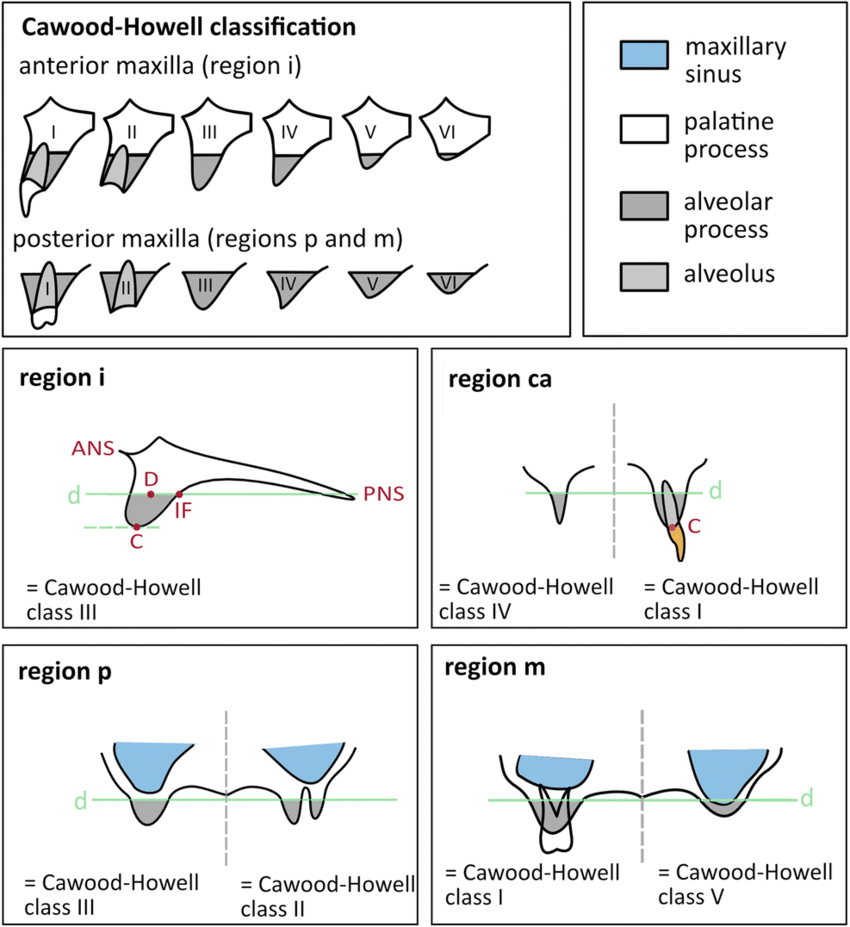

本研究に含める患者は、結果の妥当性と関連性を確保するため、いくつかの基準を満たす必要があった。対象は 35歳から80歳まで の患者で、Cawood 分類 V または VI に該当する重度上顎骨萎縮と診断された者とした。すべての参加者は、スクリュー固定式ブリッジによる補綴を伴う骨膜下またはザイゴマインプラント治療を受けていた。術前および術後の CBCT画像を含む完全な治療記録が必須条件であり、術後少なくとも 5年間のフォローアップを受けていることが求められた。さらに、インプラントの予後に影響を与える可能性のある 制御不能な全身疾患が存在しない良好な全身健康状態 であることが前提条件とされた。

参考資料:Cawood-Howell 分類 歯槽堤の分類をクラスⅠからクラスⅥまで分けている